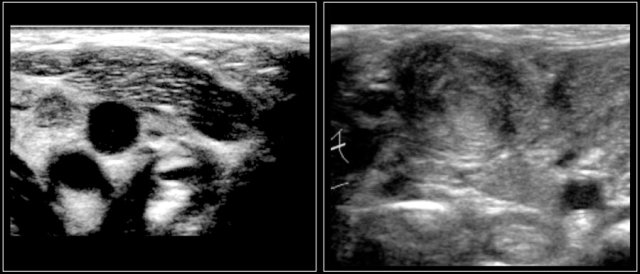

On ultrasound the affected nodes are round, homogeneously hypoechoic and the normal echogenic hilum is absent.

The images are of a fourteen-year-old boy with a painless swelling in the left neck.

The ultrasound shows several enlarged hypoechoic lymhnodes, that lack an hyper-echoic hilum.

Here another fourteen-year-old boy with a painless swelling in the left neck.

Ultrasound showed several enlarged lymhnodes.